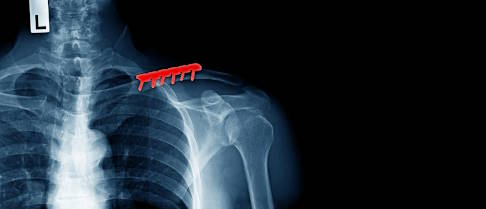

Röntgenbild: Das Schlüsselbein ist mittig gebrochen. Die Bruchstücke sind gegeneinander verschoben (disloziert). © Anton, Adobe

Um seine Verdachtsdiagnose zu bestätigen, wird der Orthopäde oder Unfallchirurg ein Röntgen veranlassen. Auf dem Röntgenbild ist in der Regel deutlich zu erkennen, an welcher Stelle und wie das Schlüsselbein gebrochen ist. Der Arzt ermittelt die Anzahl der Bruchstücke und ob diese sich gegeneinander verschoben (disloziert) haben. Dies ist wichtig für die Therapie, da gering verschobene Brüche tendenziell auch konservativ behandelt werden können. Stärker verschobene Brüche sollten eher operativ gerichtet und fixiert werden. In einigen Fällen ist zudem eine Untersuchung mittels CT notwendig. Außerdem muss der Arzt Begleitverletzungen an Gefäßen, Nerven und an der Lunge sowie Rippenfrakturen ausschließen.